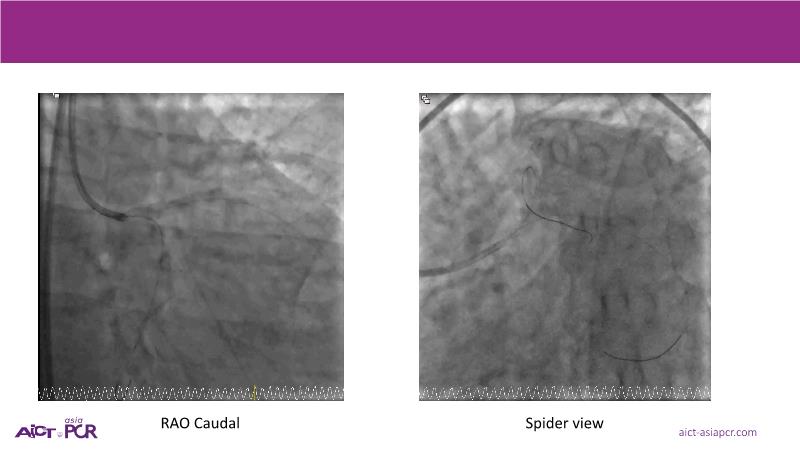

Focus on the evolving role of drug-coated balloons (DCB) in complex PCI, extending their use beyond traditional indications to challenging coronary lesions and high-risk patient populations. This session reviews clinical data from the SCAAR Prevail registry and discusses the evidence journey supporting broader advocacy for DCB in bifurcations, ACS, STEMI, multivessel disease, diabetes, and calcified lesions.